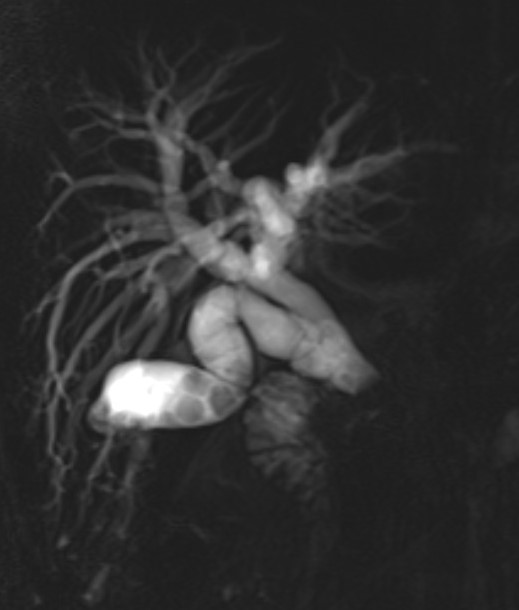

Our Post CCT/Senior Complex Benign PB & Robotic Fellowship at @UHDBTrust is now open for applicants to start from Aug 2026.

Gain experience in advanced laparoscopic and robotic benign PB surgery. In addition, fellows will develop skills in laparoscopic and robotic hernia surgery including complex abdominal wall hernias as well as training in ERCP.